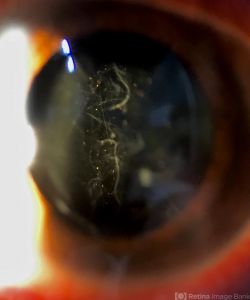

Slit lamp examination of the anterior segment should be completed prior to dilation. Examination of the anterior vitreous for pigment (Schaffer's sign) or vitreous hemorrhage is critical. A thorough fundus examination to include indirect ophthalmoscopy with scleral depression and visualization to the ora serrata should also be completed. A detailed drawing describing the detachment with location of retinal pathology may be documented.

- Shafer’s sign (“tobacco dust”) — pigment granules in the anterior vitreous that come from the RPE— strongly suggests a retinal break.

- ↑ "This image was originally published in the Retina Image Bank® website. Author/Photographer: Manuel Ángel Alcántara Delgado, MD. Shafer's Sign. Retina Image Bank. 2020; 45624. ©the American Society of Retina Specialists".